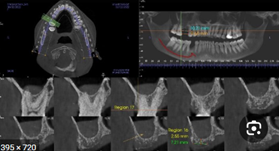

CBCT (Cone-Beam Computed Tomography)

CBCT plays a crucial role in the data acquisition process for edentulous patients. This advanced imaging technology provides three-dimensional views of the oral and maxillofacial structures, offering detailed insights into the anatomy of the edentulous jaw. Unlike traditional two-dimensional radiographs, CBCT captures critical details such as the shape and volume of the alveolar ridge, bone density, and proximity to vital anatomical landmarks like the maxillary sinus and mandibular nerve.

For edentulous patients, CBCT is indispensable for planning implant placements, assessing bone resorption, and identifying undercuts. It helps ensure accurate positioning of implants and prosthetic components while minimizing risks to surrounding structures. This high level of precision contributes to designing stable, functional, and esthetic prostheses, making CBCT an essential step in managing edentulous cases.

Step 3: Data Integration – Merging CBCT and Intraoral Scans in Planning Software

Data integration is a crucial step in the digital workflow for edentulous patients, where CBCT imaging and intraoral scans are combined using specialized treatment planning software. This integration provides a comprehensive, highly accurate 3D representation of the patient’s oral structures, enabling precise diagnosis, implant planning, and prosthetic design.

- The CBCT scan is first imported into the planning software, providing a detailed 3D view of the patient’s bone anatomy, including alveolar ridges, bone density, and vital structures like the mandibular nerve and maxillary sinus.

- However, CBCT scans alone do not capture soft tissue details or the prosthetic relationship, necessitating the integration of intraoral scans.